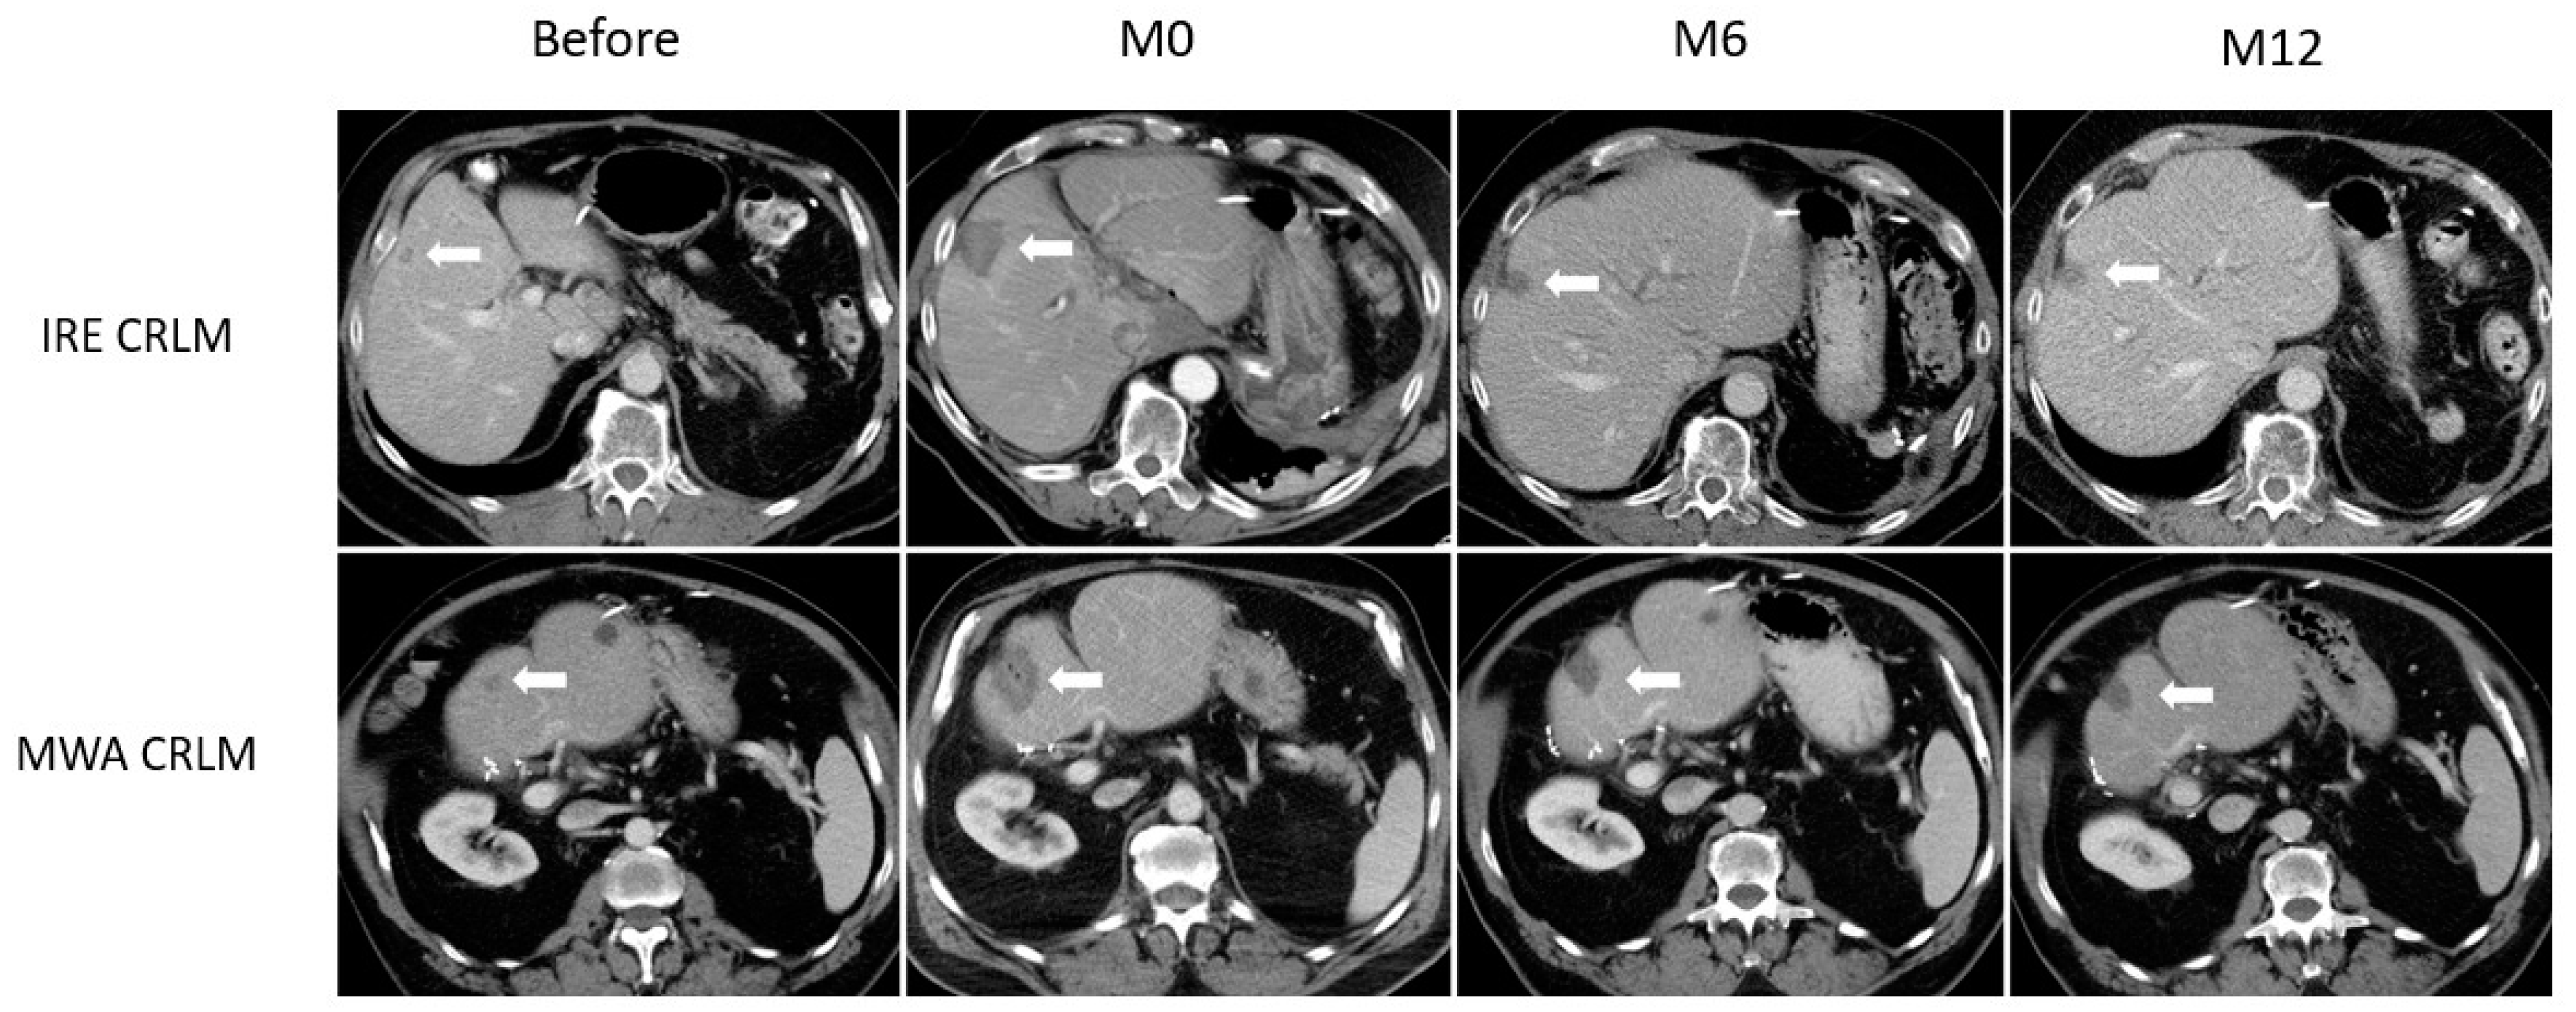

| CRLM | IRE | 0 | 705.65 | 0.615 | 0.42–0.9 | <0.01 |

| MWA | 0 | 1147.19 | ||||

| IRE | 6 | 150.57 | 0.204 | 0.1–0.415 | ||

| MWA | 6 | 739.00 | ||||

| IRE | 12 | 23.64 | 0.045 | 0.009–0.219 | ||

| MWA | 12 | 525.13 |